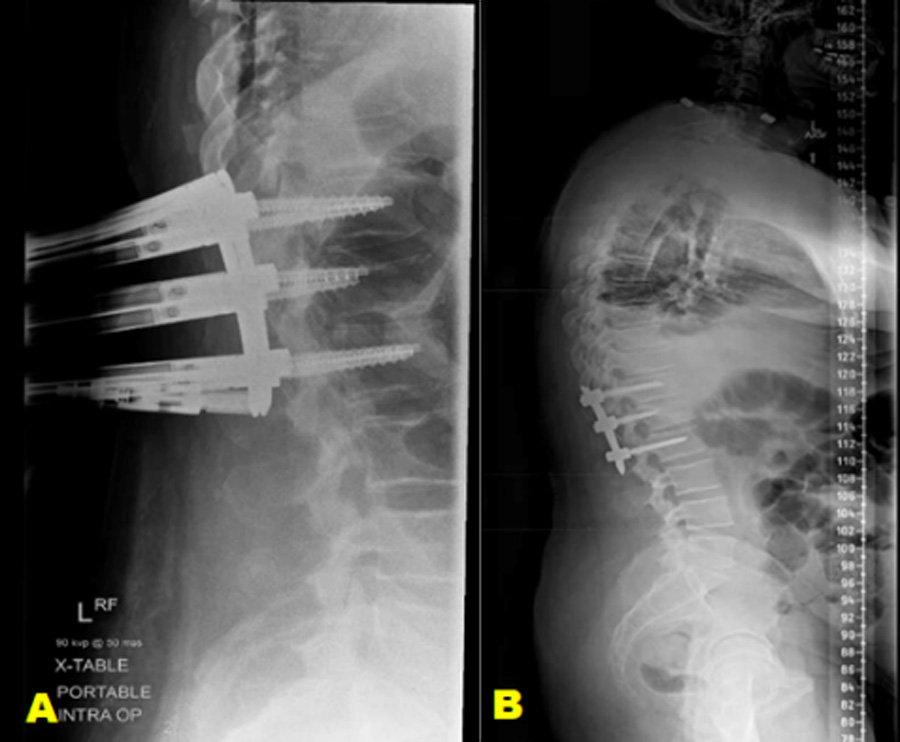

Example case 2: neurologically intact patient

Figure 2. A 28-year-old male patient has a history of recurrent dislocation of the right shoulder, for which he underwent surgery three years ago. He was involved in a traffic accident, colliding with a car while riding his motorcycle and being thrown from it.

Severe pain in his back and left forefoot, as well as deformity and functional weakness in his right shoulder. The patient was neurologically intact and temporary loss of consciousness.